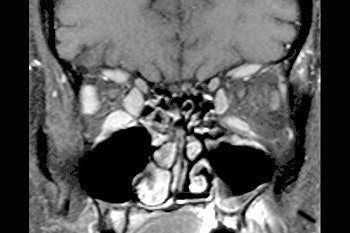

The patient underwent treatment with the antibiotic doxycycline for three weeks. Three months later, post-treatment MR exams showed complete resolution of the homogenous muscle thickening, and some inflammatory changes in the sinuses that eventually resolved themselves.

| Axial contrast-enhanced, fat-suppressed T1-weighted image through the orbits, post-treatment with doxycyline, demonstrates complete resolution of the previously noted homogeneous muscle thickening. There remain scattered inflammatory changes in the ethmoid sinuses and the left maxillary sinus. Images courtesy of Dr. Peter Som. |